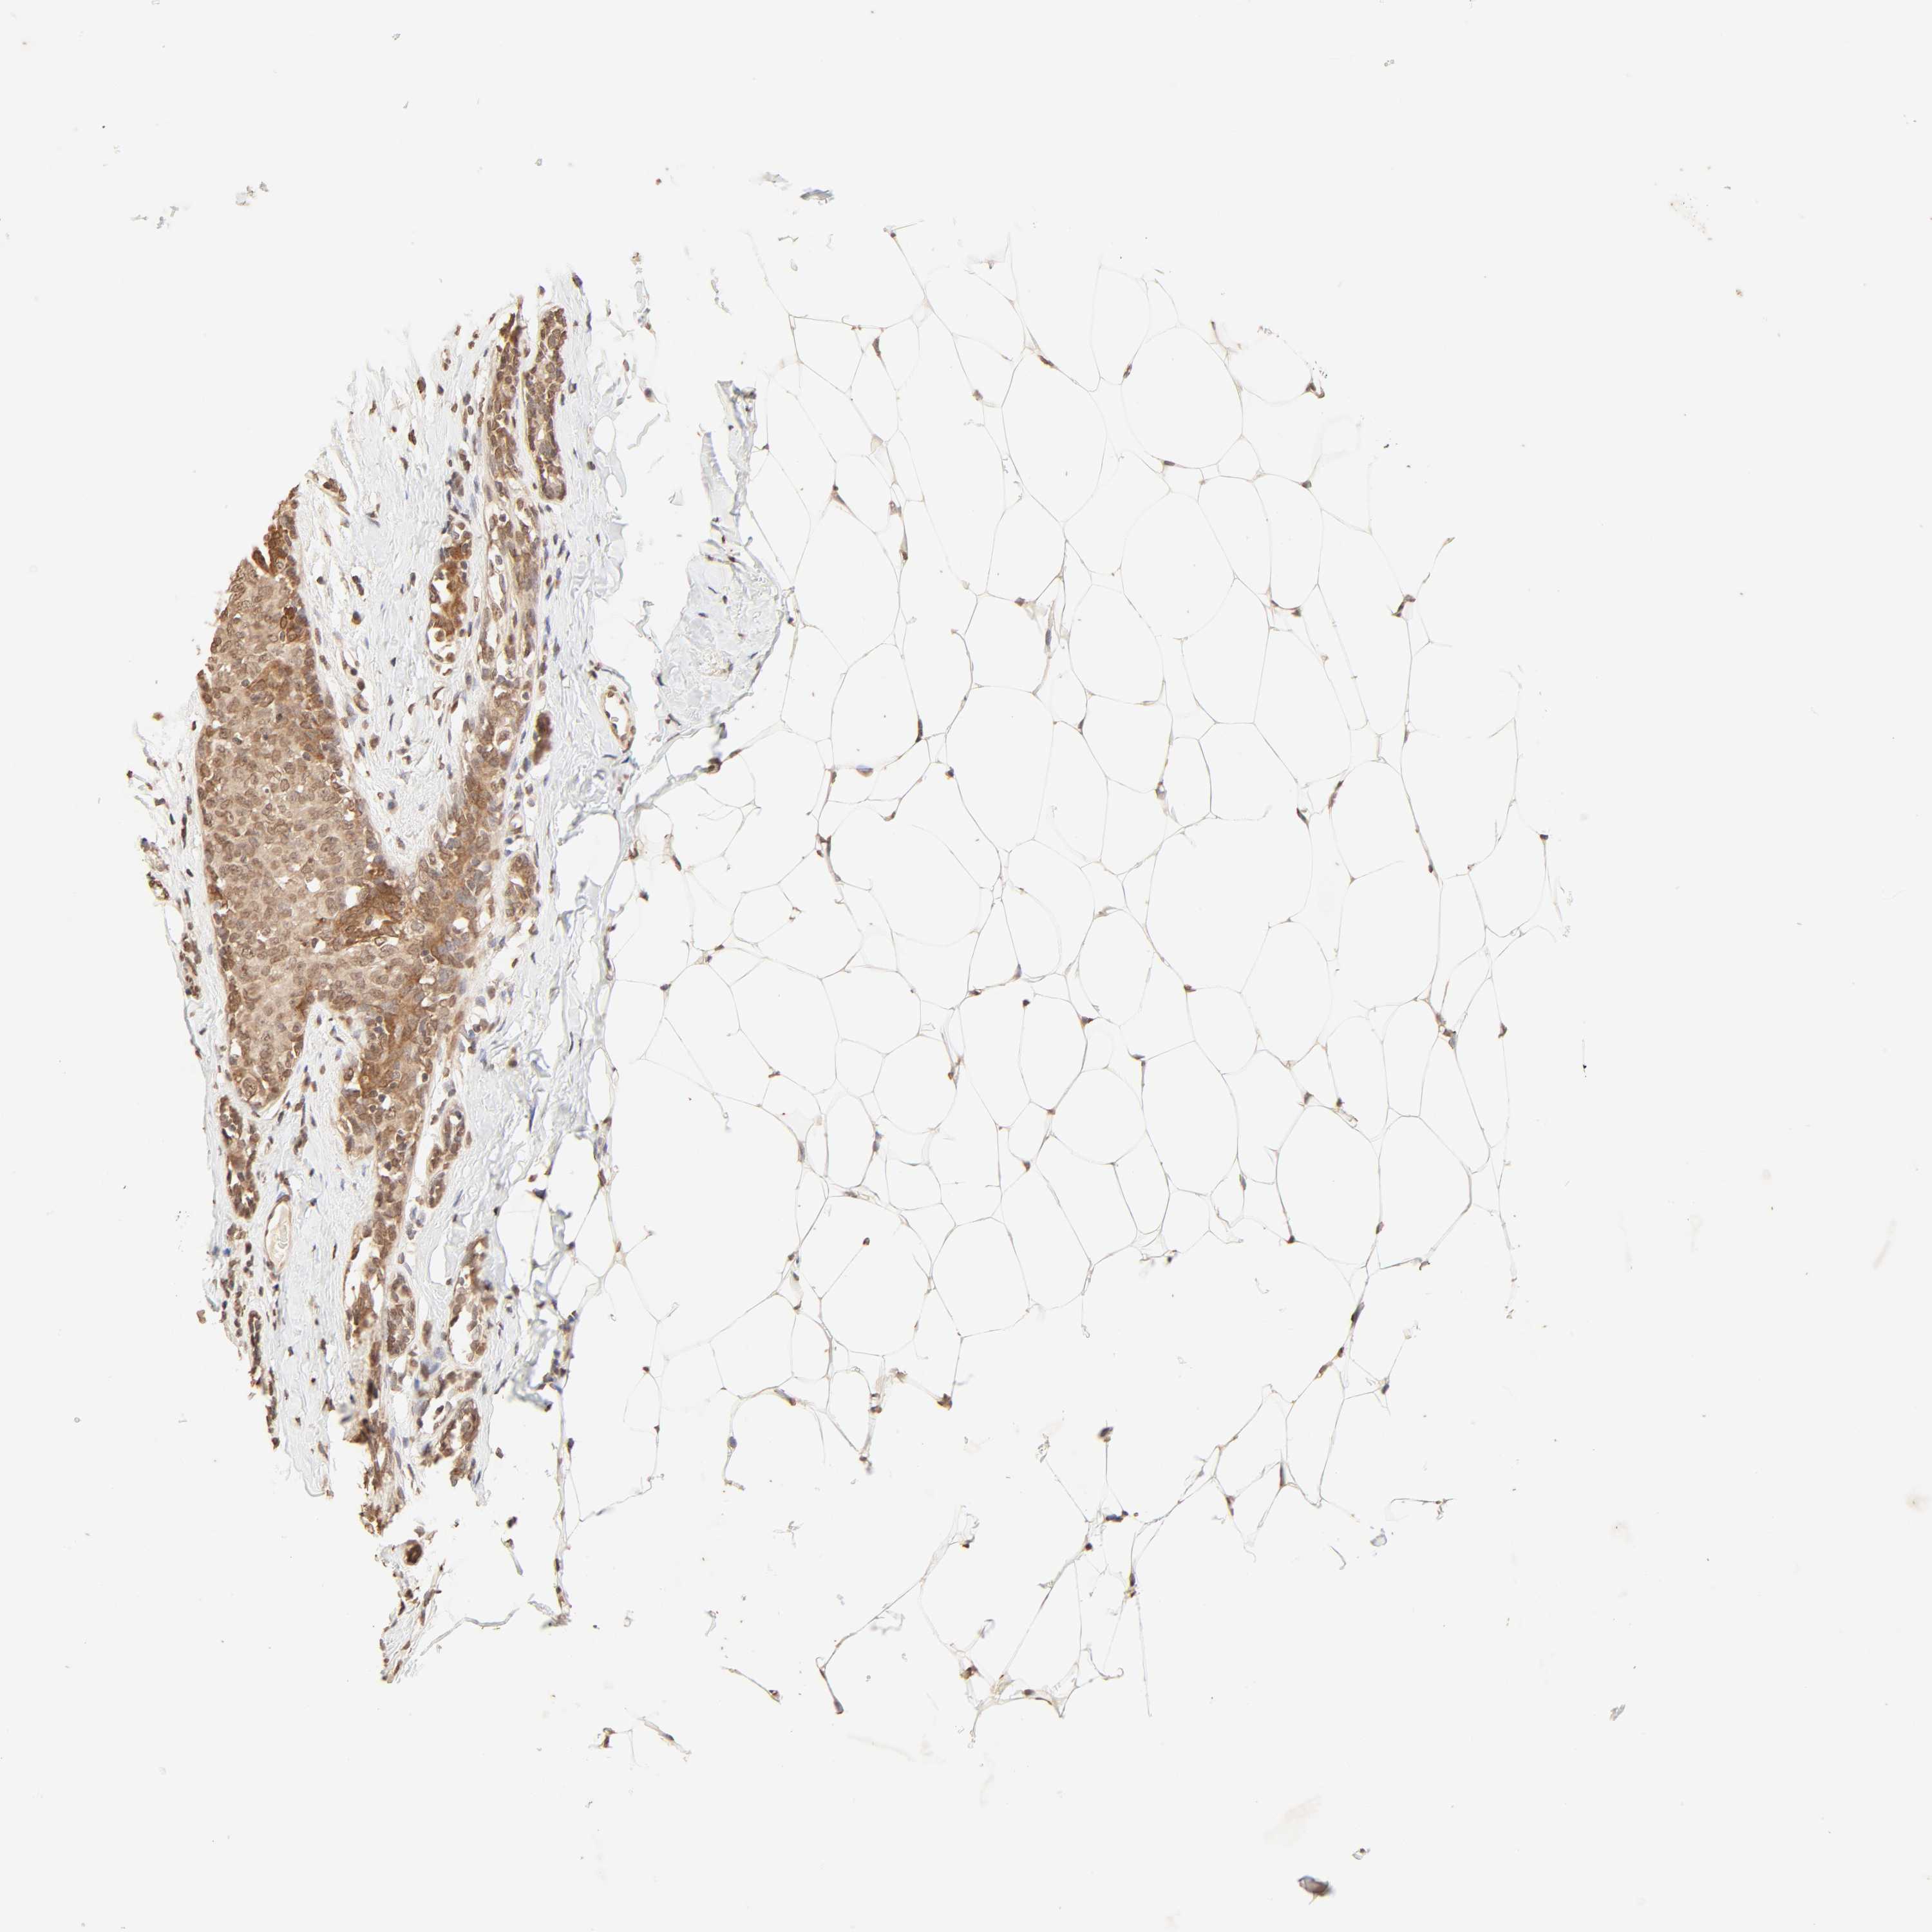

CANCER BREAST CANCER Show tissue menu

BRCA TCGA BRCA VALIDATION PROTEIN EXPRESSION

ANTIBODIES

AND

VALIDATION